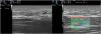

Una mujer de 32 años acude por induración en miembros superiores y cara externa de rodillas, asociado a limitación de movimientos de 3 meses de evolución (fig. 1A). La ecografía cutánea (sonda lineal 18MHz, equipo Esaote, MyLab™ Class C) mostró engrosamiento de la fascia muscular, alteración de la ecoestructura de la hipodermis superficial y una dermis sin hallazgos patológicos (fig. 2A). La elastografía reflejó un aumento de rigidez de la fascia muscular (fig. 2B). Con estos hallazgos se sospechó de fascitis eosinofílica (FE), confirmándose con resonancia magnética nuclear y biopsia de fascia. La FE es un raro trastorno fibrosante, que se manifiesta como una seudocelulitis o signo de «piel de naranja» junto con el signo del surco. El diagnóstico definitivo es con biopsia que incluya hipodermis y fascia muscular. Existen pocas publicaciones sobre la utilidad de la ecografía en el diagnóstico de la FE. Se apreciará un aumento del grosor de la fascia muscular, pudiendo haber o no alteraciones en hipodermis. La elastografía es una técnica basada en la detección de los cambios de elasticidad en los tejidos mediante el ultrasonido. Presentamos un caso donde la ecografía cutánea con elastografía ha sido de utilidad para orientar el diagnóstico de la FE, así como su potencial papel en el seguimiento para valorar la respuesta terapéutica.